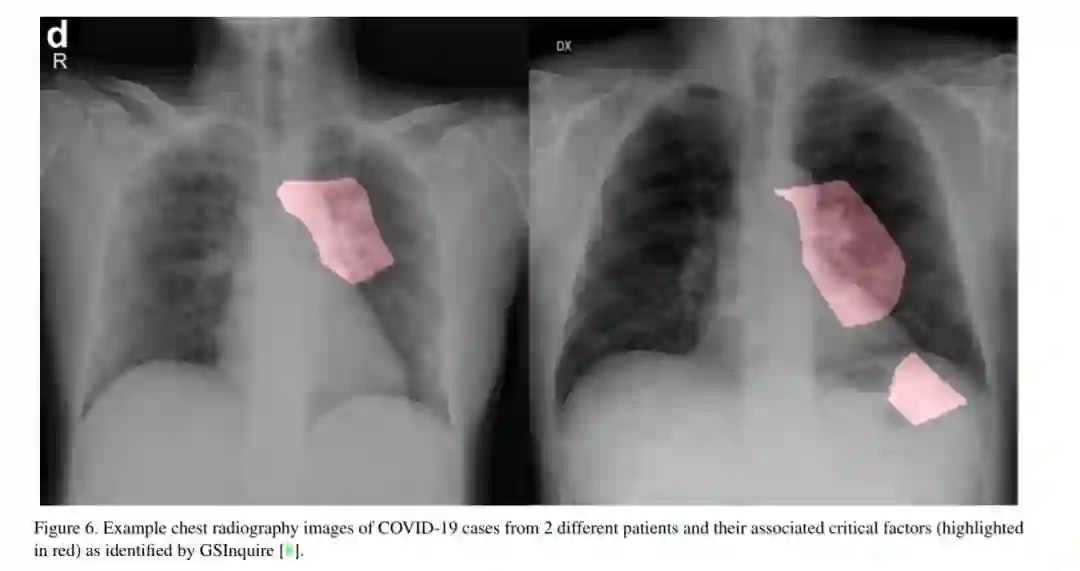

COVID-19大流行继续对全球人口的健康和福祉产生破坏性影响。与COVID-19作斗争的一个关键步骤是对受感染患者进行有效的筛查,其中最关键的筛查方法之一是使用胸片进行放射成像。基于此,许多基于深度学习的人工智能(AI)系统被提出,结果显示在使用胸片图像检测COVID-19感染患者的准确性方面很有希望。然而,据作者所知,这些开发的人工智能系统是封闭的,研究社区无法对其进行更深入的理解和扩展,也无法对公众进行访问和使用。因此,在本研究中,我们引入COVID-Net,这是一种针对胸片图像中COVID-19的检测而设计的深度卷积神经网络,它是开源的,并且对公众开放。我们还描述了用于训练COVID-Net的胸片数据集,我们将其称为COVIDx,它由来自两个开放访问数据库的2839例患者的5941张前后胸片图像组成。此外,我们研究COVID- net如何使用可解释性方法进行预测,以获得与COVID病例相关的关键因素的更深入的了解,从而帮助临床医生改进筛选。决不生产就绪的解决方案,希望开放获取COVID-Net,随着描述构建开源COVIDx数据集,将杠杆,建立由研究人员和公民数据科学家们还都加快发展的高度准确的实际深度学习解决方案检测COVID-19病例和加速处理那些最需要的人。

基于迫切需要开发解决方案以帮助抗击COvID-19大流行,并受到研究社区开源和开放获取努力的启发,本研究引入COVID-Net,这是一种深度卷积神经网络设计,专门用于从公开的、向公众开放的胸片图像中检测COvID-19病例。我们还描述了用于训练COVID-Net的数据集,我们将其称为COVIDx,它由来自2839例患者的5941张前后胸片图像组成,是由包含胸片图像的两个开放访问数据库(即科恩(Cohen)和卡格尔(kaggle))。此外,我们研究COVID- net如何使用可解释性方法进行预测,以获得与COVID病例相关的关键因素的更深入的了解,从而帮助临床医生改进筛选。